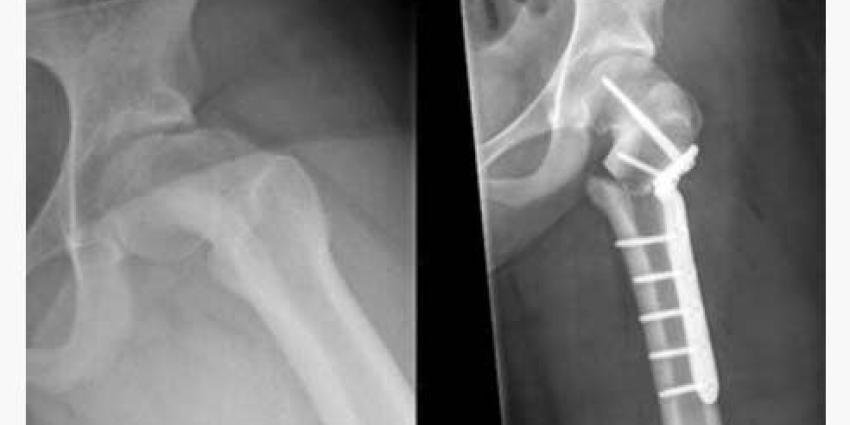

Foto: OLVG

Voor het eerst in Nederland is een 3D-geprinte plaat gebruikt om een ‘afgegleden heupkop’ te corrigeren. Orthopedisch chirurg Melinda Witbreuk van OLVG Amsterdam plaatste het plaatje op de heupkop van een 13-jarige patiënt. Hiermee is de scheefstaande heup flink gecorrigeerd en kan het 13-jarige meisje straks een stuk beter lopen.

‘Met de 3D-print van de heup was het mogelijk om voor de operatie een plaat te maken die precies bij deze heupkop past. Hiermee konden we de heup beter corrigeren en staat het been van de patiënt een stuk rechter. Een verbetering in vergelijking met de gangbare methode’, aldus dr. Melinda Witbreuk van OLVG.

Tot nu toe werden operaties aan de heupkop ‘op het oog’ uitgevoerd. Met een 2D-röntgenfoto werd bekeken waar de correctie moest plaatsvinden. De heup werd vervolgens gecorrigeerd met een standaard plaat. Sinds enkele jaren gebruiken orthopeden een 3D-CT-scan voor een betere pre- en operatieve planning.

In de voorbereiding op deze operatie heeft kinderorthopeed Melinda Witbreuk een 3D-geprint model van de heup laten maken via het 3D- innovation lab in het VUmc. Zo kon er een exact passende plaat voor een zo optimaal mogelijke correctie worden gemaakt. Ook de titanium plaat voor de correctie komt uit een 3D-printer.